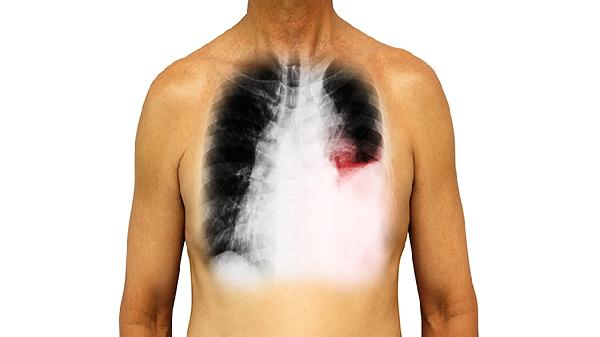

肺部片子的解读需要由专业医生通过观察肺纹理、密度变化、异常阴影等影像特征进行判断。常见异常表现主要有肺纹理增粗、结节影、斑片影、空洞形成、胸腔积液等。

肺部结节指直径小于3厘米的圆形高密度影。良性结节边缘多光滑,如结核球、错构瘤;恶性结节常呈分叶状或有毛刺,多见于肺癌。发现结节后需定期复查或进行PET-CT检查,必要时可经皮肺穿刺活检明确性质。

表现为边界模糊的云絮状阴影,多见于肺部感染性病变。细菌性肺炎多呈叶段分布,病毒性肺炎多为双侧弥漫性改变,真菌感染可出现特殊形态的晕征或空气新月征。治疗需根据病原学检查选用敏感抗生素如阿莫西林克拉维酸钾片、左氧氟沙星片等。

肺组织坏死液化后经支气管排出可形成空洞。结核性空洞壁较薄且内壁光滑,周围常见卫星灶;癌性空洞壁厚薄不均且内壁凹凸不平;肺脓肿空洞多伴有液平面。确诊需结合痰培养、肿瘤标志物等检查。

胸膜腔内液体异常积聚时,X线片可见肋膈角变钝或大片致密影。漏出液多见于心力衰竭、低蛋白血症,渗出液常见于结核性胸膜炎、恶性肿瘤。诊断性胸腔穿刺可明确积液性质,治疗包括利尿剂如呋塞米片、胸膜固定术等。